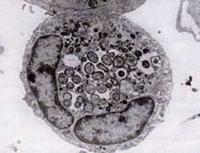

Ultrastructure of A.phagocytophilum by transmission electron microscopy. Photo by V.Popov, reprinted from Dumler JS et al. Human granulocytic anaplasmosis and Anaplasma phagocytophilum. Emerg Infect Dis;11:1828-34.

Like Ehrlichia species, Anaplasma organisms are small, gram-negative, and intracellular. A. phagocytophilum targets neutrophils, alters their function in the host, and forms morulae within vacuoles. Most of the damage it causes appears to be related to host inflammatory processes, as there is little evidence of a correlation between the number of organisms and host disease severity.